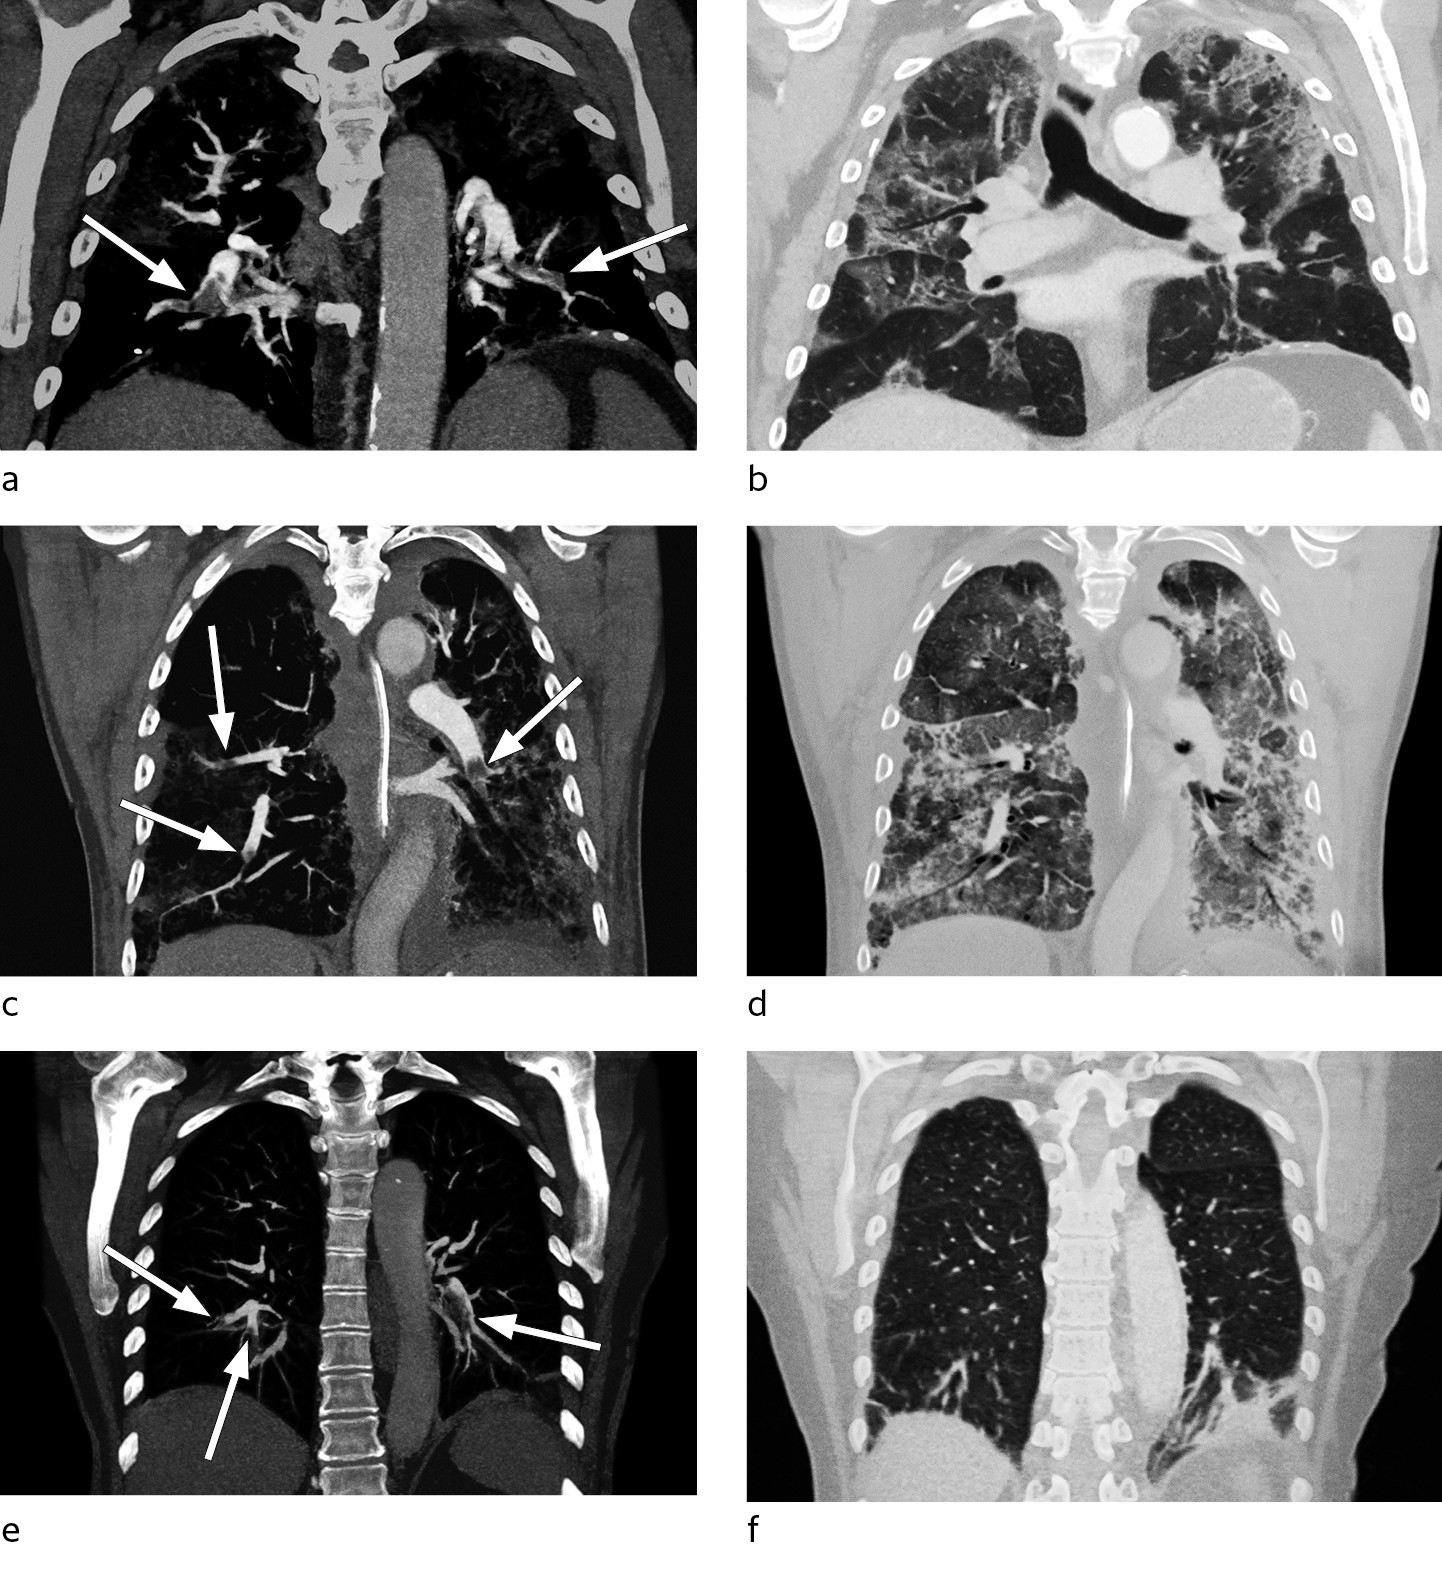

Han hadde økende oksygenbehov fra dag 9, med behov for 10 l/min på reservoarmaske for å holde SpO2 > 94 %. Han ble gradvis mer medtatt og sliten. Røntgen thorax dag 12 viste vesentlig uendret utbredelse av lungefortetninger. Grunnet manglende bedring i oksygenering og vedvarende sterkt forhøyet D-dimer til verdier > 10 mg/l FEU (figur 1) ble det dag 15 utført CT pulmonal angiografi. Denne avdekket bilaterale segmentale og subsegmentale lungeemboluser, i tillegg til utbredte infeksiøse fortetninger (figur 2a-b). Etter oppstart av antikoagulasjonsbehandling (enoksaparin 100 mg × 2) ble oksygenbehovet gradvis redusert og allmenntilstanden raskt bedre.

Med bakgrunn i rapporter om økt forekomst av venøse tromboemboliske hendelser hos intensivpasienter med covid-19 valgte vi å øke profylaksedosen av enoksaparin til 40 mg × 2. Dag 7 steg D-dimerverdiene fra 2,8 til 24 mg/l FEU. Ferritinnivået var > 2 000 µg/ml, og man startet behandling med interleukin-1-reseptorantagonist (anakinra) dag 10. Fram til dag 13 så man radiologisk progrediering av lungefortetninger, mens D-dimerverdien falt etter oppstart av anakinra (figur 1). Grunnet ny D-dimerstigning fra 16 mg/l FEU til 26 mg/l FEU ble det dag 16 utført CT pulmonal angiografi. Man fant da bilaterale perifere lungeemboluser og utbredte fortetninger i alle lapper (figur 2c-d). Det ble startet antikoagulasjonsbehandling (enoksaparin 100 mg × 2), men etter et langvarig forløp med stasjonær alvorlig lungesvikt døde pasienten dag 22.

En tidligere frisk kvinne i 70-årene gjennomgikk en ukes sykdom med lett tørrhoste og øvre luftveissymptomer. Det ble påvist sars-CoV-2 i luftveissekret etter to dager. Etter en to ukers periode uten symptomer tilkom det på ny tørrhoste, og pasienten ble innlagt dag 23 dager etter symptomdebut med aktivitetsdyspné og takypné. Det forelå ved innkomst respiratorisk alkalose, og D-dimerverdien var 1,9 mg/l FEU. Røntgen thorax viste normale funn. Det ble utført CT pulmonal angiografi, som avdekket bilaterale segmentale og subsegmentale lungeemboluser med affeksjon av alle lungelapper, uten funn av infeksjonssuspekte fortetninger (figur 2e-f). Hun fikk peroral antikoagulasjonsbehandling (apiksaban 10 mg × 2) og ble utskrevet da hun var i bedring.